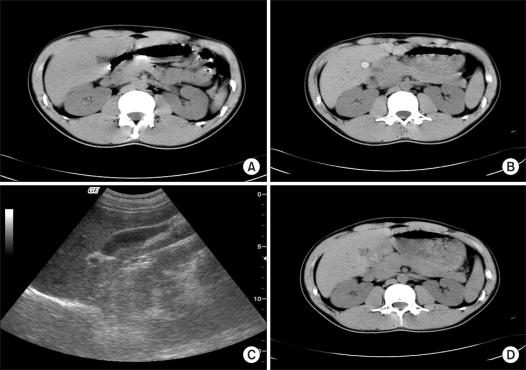

Ceftriaxone is a commonly used antibiotic due to some of its advantages. Reversible gallbladder (GB) sludge or stone has been reported after ceftriaxone therapy. Most of these patients have no symptom, but the GB sludge or stone can sometimes cause cholecystitis. We experienced two patients who had newly developed GB stones after ceftriaxone therapy for diverticulitis and pneumonia, and this resolved spontaneously 1 month after discontinuation of the drug. Awareness of this complication could help to prevent unnecessary cholecystectomy.

由于某些优点,头孢曲松是一种常用的抗生素。已有报道称,头孢曲松治疗后会出现可逆性胆囊(GB)泥沙样沉淀或结石。这些患者大多数没有症状,但GB泥沙样沉淀或结石有时会引起胆囊炎。我们遇到了两名患者,他们在接受头孢曲松治疗憩室炎和肺炎后新出现了GB结石,停药1个月后结石自行消退。认识到这种并发症有助于预防不必要的胆囊切除术。